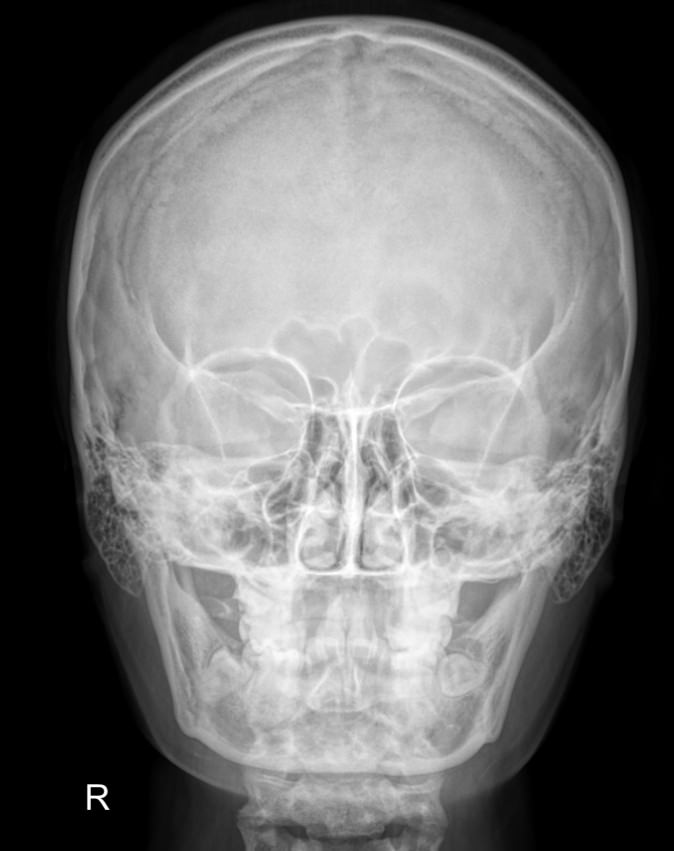

В протоколе рентгенолог описывает следующие элементы:

• Кости, их форма, размеры, соотношение, видимость швов;

• Толщина костей в разных участках;

• Контуры внешние и внутренние;

• Следы «пальцевых вдавлений» и сосудистый рисунок;

• Состояние турецкого седла, его числовые значения;

• Наличие воздуха пазухах и их состояние;

• Переломы;

• Участки обызвествления;

• Новообразования.